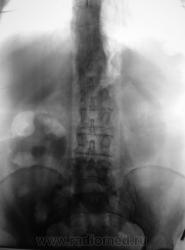

Пациент направлен на внутривенную урографию. Диагноз - "Мочекаменная болезнь?". Врач УЗИ сообщил, что "камни" с обеих сторон. По поводу картины сильно не распространялся.

1. Пациент? Или пациентка? (судя по ширине малого таза и наличия в нем обызествления характерного в большей степени для обызествленного фиброматозного узла);

2.Крупный коралл правой почки и камень лоханки левой почки;

3.Блок правой почки, как следствие МКБ (камни в средней трети правого мочеточника);

4. Отток слева не нарушен;

5.Округлый дефект выполнения в области устья правого мочеточника вполне может быть обьяснен наличием уретероцеле, а тогда станет понятна и причина камнеобразования справа.

Пациентка, наша коллега, врач.

Фрагмент с мочевым пузырем.

Пациентку сегодня прооперировали в областной больнице. Со слов начмеда знаю только одно - удалили почку.

Сегодня говорил с коллегой - пациентной.

Да, камень в мочеточнике, гидронефроз, почка удалена.

В мочевом пузыре - доброкачественная опухоль.